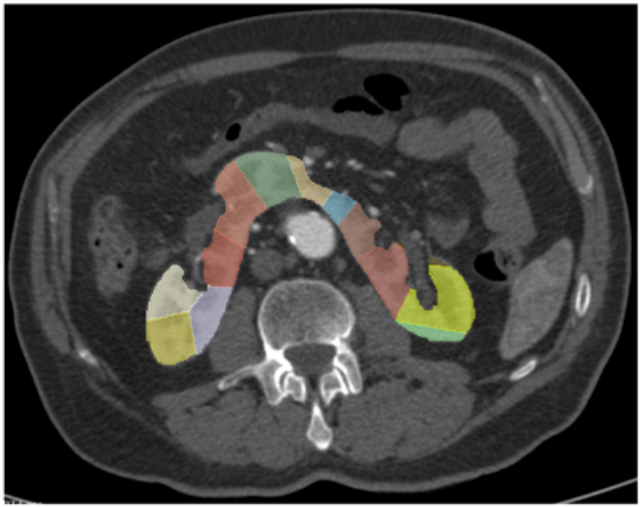

Semiautomatic volume measure of kidney vascular territories on CT angiography to plan aortic aneurysm repair in patients with horseshoe kidney

Journal of European Radiology, 2024

By developing a semiautomatic CTA-based model to measure kidney vascular territories, we enable precise preoperative planning for aortic aneurysm repair in patients with horseshoe kidney, reducing risk of postoperative renal damage